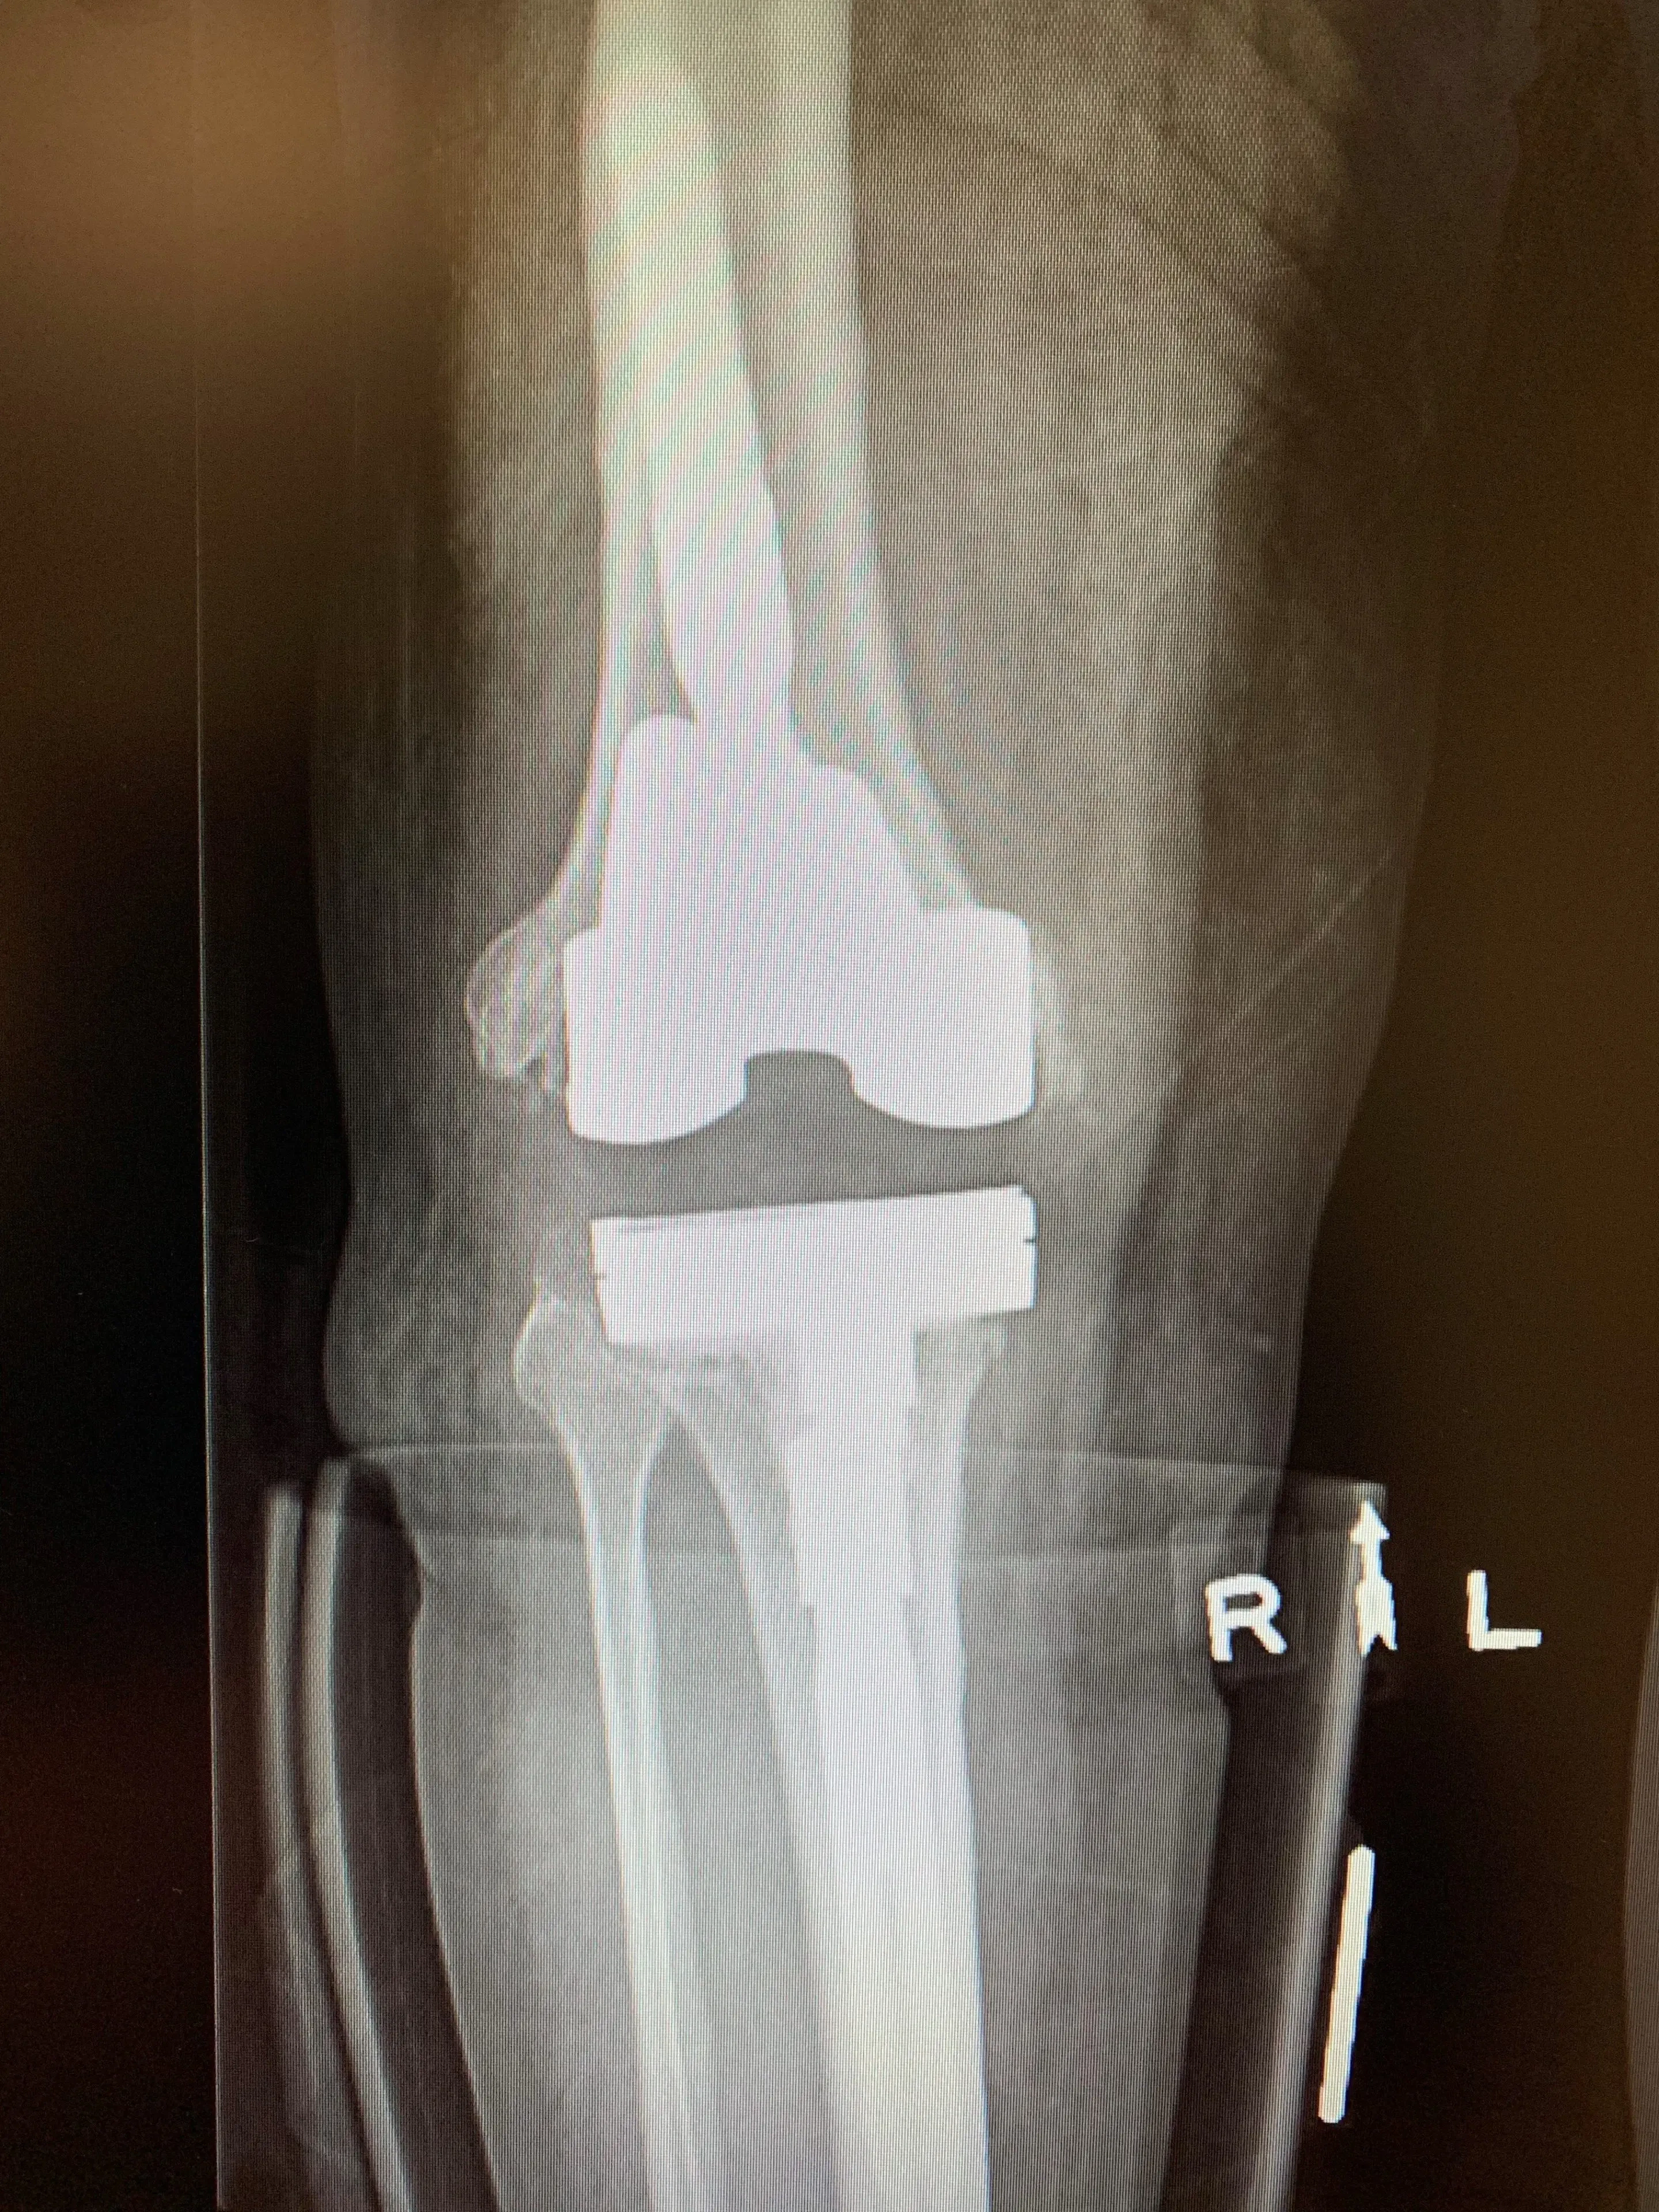

X-rays revealed an appropriately sized and positioned Revision Total Knee Replacement prosthesis with a resurfaced patella and no obvious signs of loosening or periprosthetic fracture.

Pre-op

Treatment of infected knee replacement. A staged reconstruction in a 64-year-old male.